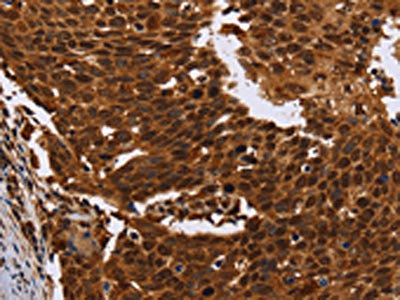

The image on the left is immunohistochemistry of paraffin-embedded Human colon cancer tissue using CSB-PA569454(FANCF Antibody) at dilution 1/60, on the right is treated with fusion protein. (Original magnification: ×200)